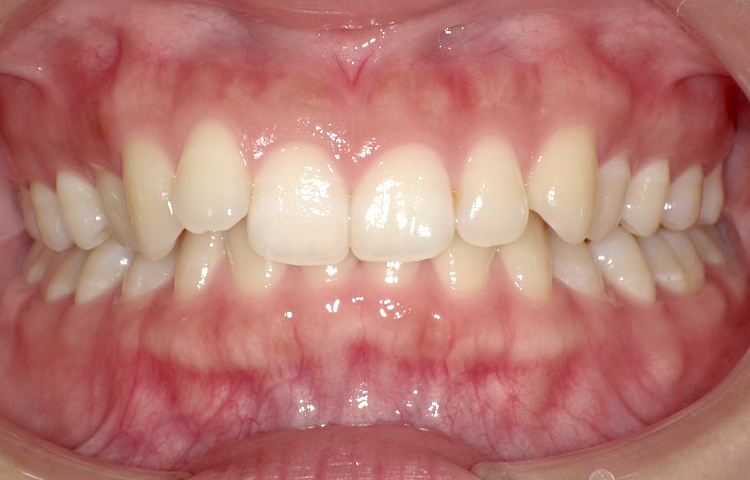

治療後

| 主訴 | 上下の前歯のゆがみ(叢生)を治したい |

|---|---|

| 治療 期間 |

約6ヶ月 |

| 治療費 | 330,000円(税込)/調整費用別途 |

| 治療 内容 |

ワイヤープチ矯正で上下の前歯の矯正治療を行った。 前歯の歯と歯の間をごく少量削り、前歯計8本の向きを揃えた。 見た目が綺麗になったことははもちろん、 磨きにくかったところが磨きやすくなった。 |

| 治療の リスク |

歯と歯の間を削ることでスペースを確保するので、 場合によっては歯が染みる症状が出ることがある。 |